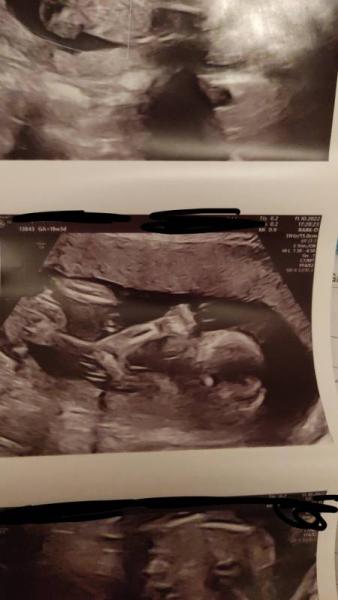

gestern hatte ich das grosse Screening in der 19.ssw. Alles war super auĂer ein White Spot, aber das hatte ich bei meiner ersten Tochter auch und ist nichts schlimmes. Und aus den 80 Prozent Jungen wurde jetzt mit hoher Wahrscheinlichkeit ein MĂ€dchen.Der Schniepel war einfach weg, obwohl er vor 4 Wochen auf Video so gut zu sehen war und keine Zweifel bestanden ich freue mich dennoch, aber man muss nun umplanen

bin gespannt was bei der Feindiagnostik herauskommt.Liebe GrĂŒĂe an alle